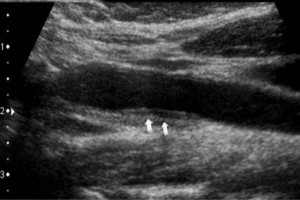

Diplomados en Ultrasonografía